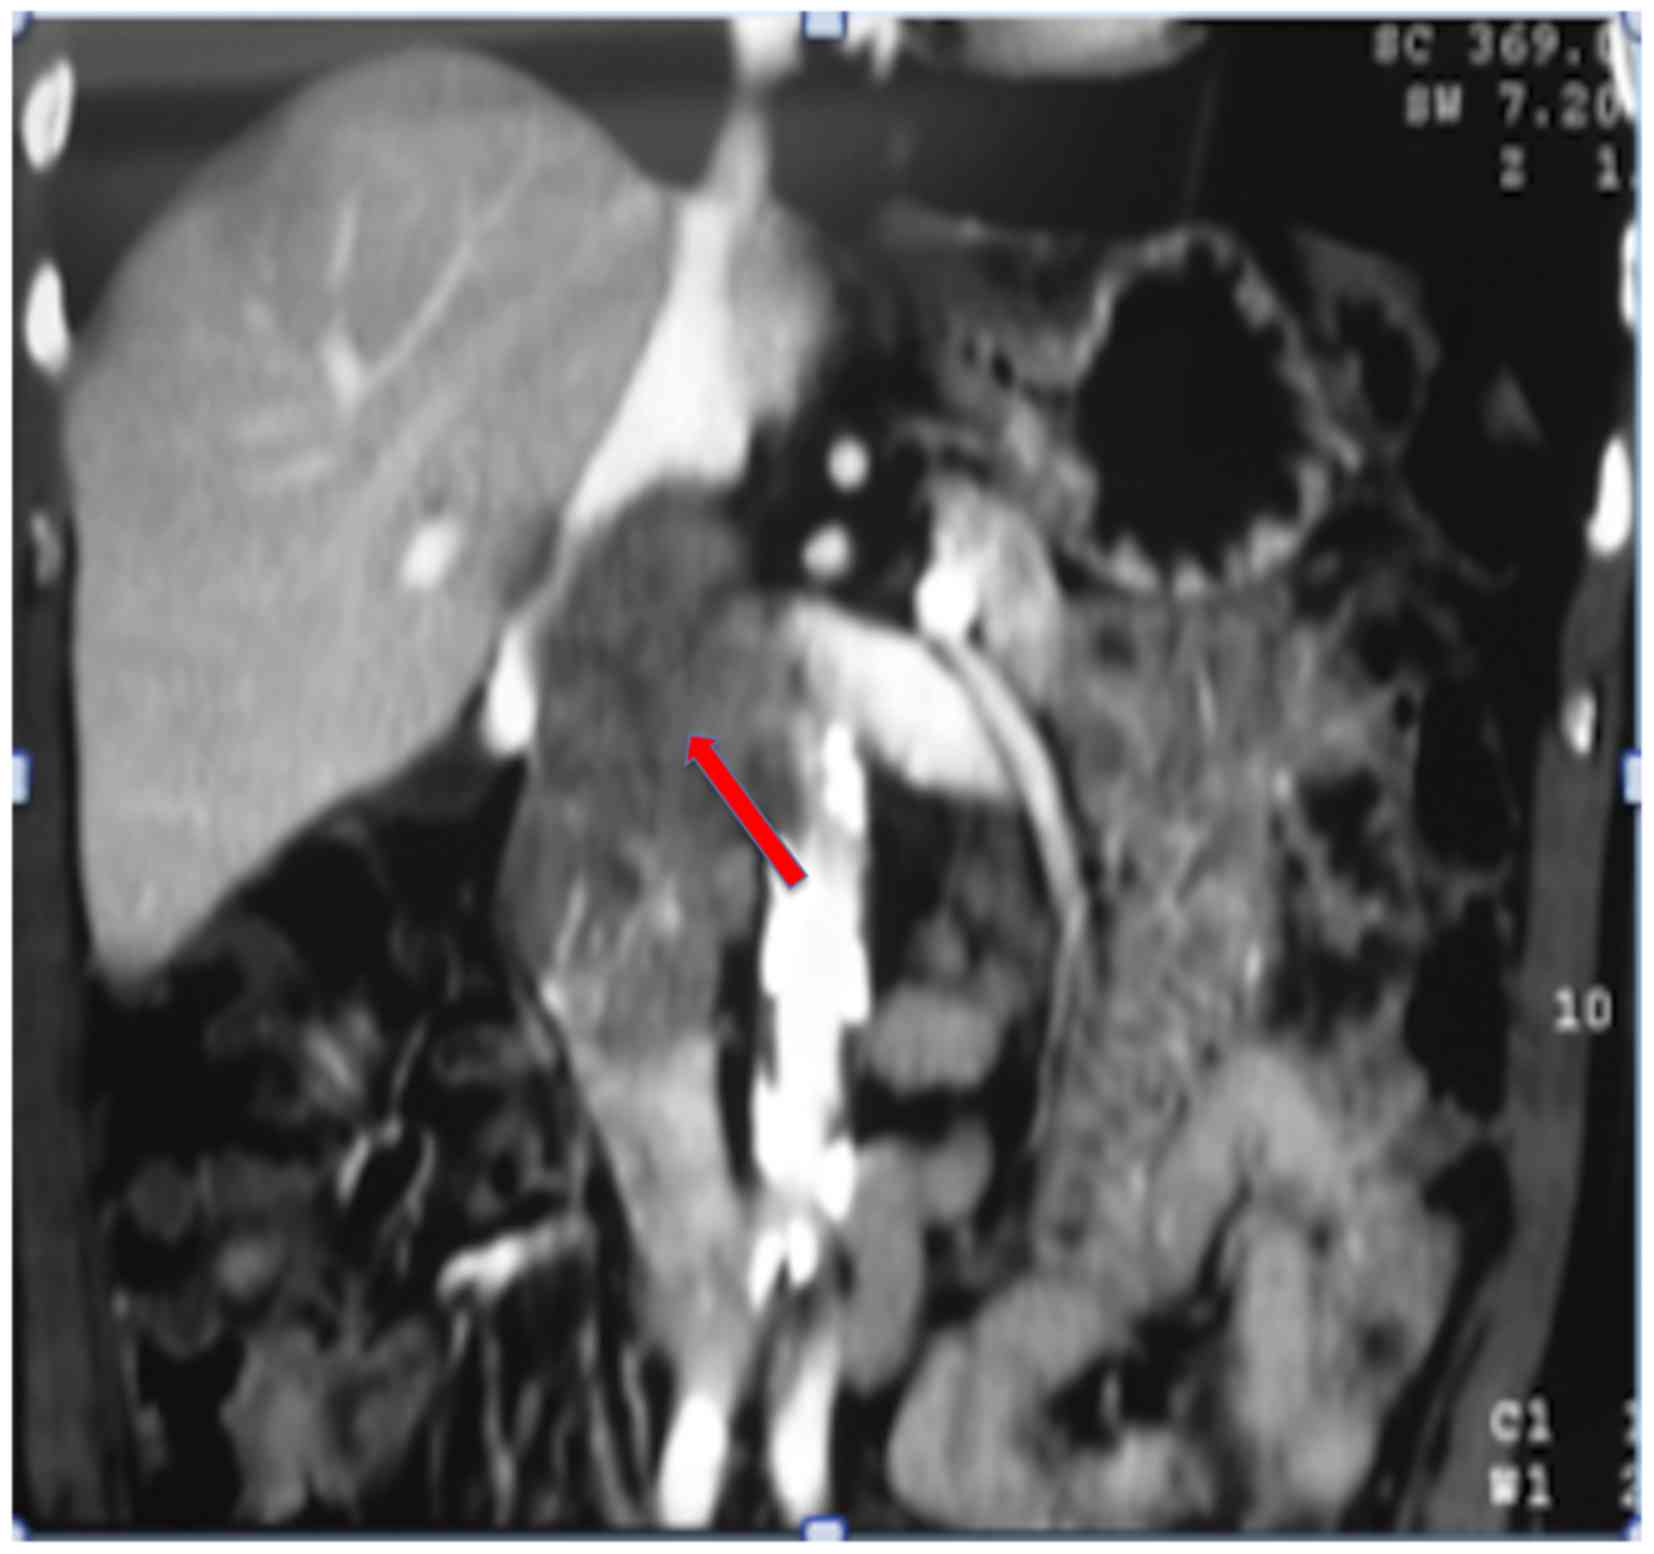

A 78-year-old male with a 4-month history of abdominal pain was admitted to the pancreas and biliary tract surgery service at the Clinics Hospital affiliated to the University of São Paulo (São Paulo, Brazil). A computed tomography (CT) scan (Fig. 2) of the abdomen revealed a 7.0 cm mass between the IVC and duodenum, which was suspected as a primary IVC tumor. The patient was referred to the surgical oncology group at the São Paulo Cancer Institute (São Paulo, Brazil) for further evaluation. The vascular surgery and surgical oncology teams planned the operative resection together. Exploration was performed via a midline incision. The mass was identified arising from the IVC and involved the lower and middle segment, and the right renal vein. Proximal and distal controls from the IVC were obtained (Fig. 3), and the mass and the right kidney were dissected free. The tumor was excised en bloc with 9.5 cm of the IVC and the right kidney with a 10 mm margin. IVC reconstruction was performed using an 18-mm Dacron prosthetic graft. Left renal vein reconstruction using a polytetrafluoroethylene (PTFE) prosthetic graft was performed (Fig. 4). The patient was heparinized. While on systemic anticoagulation, the patient was submitted to reoperation due to a postoperative retroperitoneal hematoma. The hematoma was evacuated and no active bleeding was identified. The patient was discharged home on warfarin. Surgical pathological examination demonstrated a multilobulated high-grade 8.0 cm LMS of the IVC with negative surgical margins. The patient remained well for 28 months; however, multiple pulmonary nodules were identified in the routine surveillance CT scan. The patient subsequently underwent multiple metastasectomies with subsequent recurrences. The patient succumbed to the disease 57 months following the original resection.

![]() | Figure 3.Retroperitoneal tumor dissected in a patient with leiomyosarcoma of the inferior vena cava. |